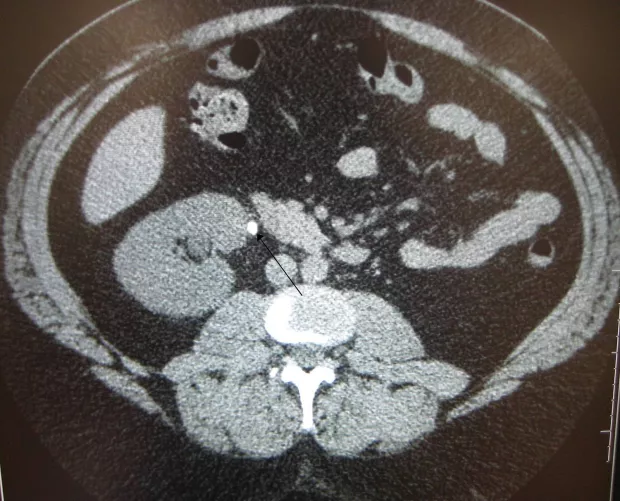

CT-rétegfelvétel

Húgyvezetékben elakadt vesekő CT-felvételen, nyíllal jelölve (szerző: James Heilman, MD; liszensz: CC BY-SA 3.0, Wikimedia Commons)